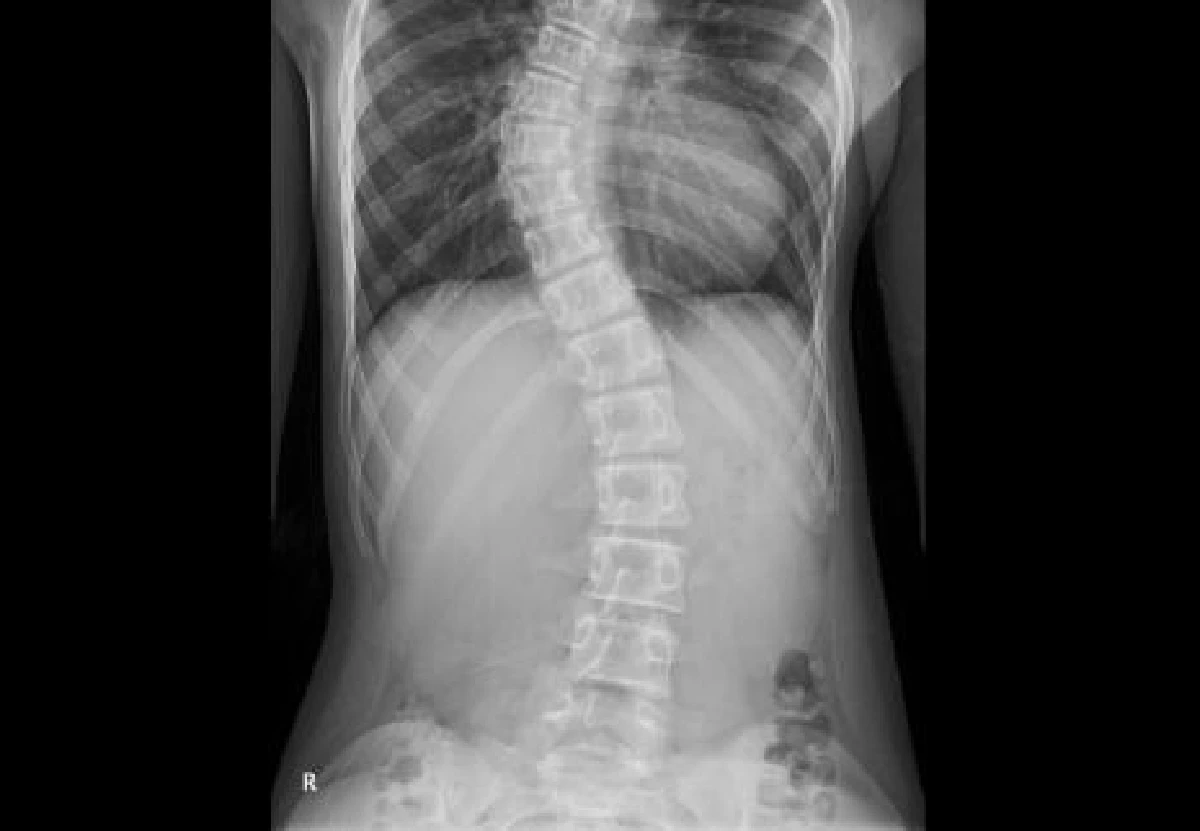

เมื่อวันที่ 9 มิ.ย. สังคมพูดคุยเตือนภัยผู้ปกครองสังเกตบุตรหลานหลังสมาชิกเว็บไซต์พันทิปชื่อ “pimmyaom” ได้โพสต์กระทู้ชื่อ “ลูกสาวของแม่กำลังก้าวผ่านความเจ็บปวดจากการผ่าตัดกระดูกสันหลังคดในวัย 11 ขวบ 7 เดือน” ซึ่งในปัจจุบันเด็กๆ สมัยนี้ป่วยเป็นโรคดังกล่าวเป็นจำนวนมาก โดยเจ้าของกระทู้ระบุเล่าย้อนกลับไปในช่วงที่ลูกสาวอายุ 10 ขวบ เมื่อปีที่แล้วในวันที่ 28 มีนาคม 2561 มักจะมีอาการบ่นว่าปวดหลัง ปวดไหล่ จึงแก้ไขให้ด้วยการนวด เนื่องจากเข้าใจว่าสาเหตุเกิดจากการที่สะพายกระเป๋านักเรียนหนักเกินไป แต่ความจริงสาเหตุของการเกิดโรคกระดูกสันหลังคดมีหลายสาเหตุมาก กระทั่งเริ่มสังเกตเห็นหลังของลูกสาวช่วงสะบักแขนข้างขวาโค้งออกมาผิดปรกติ ไม่เรียบ ทำให้ตัดสินใจเข้าพบแพทย์และเมื่อเอกซเรย์พบว่า กระดูกสันหลังคดประมาณ 20 องศา

วันที่ 31 ต.ค.2561 ผลเอกซเรย์ครั้งที่ 2 กระดูกสันหลังคดเพิ่มเป็น 30 องศา ต่อมาจากนั้นอีก 6 เดือน ตรวจพบว่ากระดูกคดเพิ่มเป็น 40 องศา แพทย์ลงความเห็นอาจจะต้องใส่เสื้อเกราะดามไว้หรือผ่าตัด แต่ที่โรงพยาบาลไม่สามารถผ่าตัดได้จากเครื่องมือที่ไม่พร้อมและที่สำคัญผู้ป่วยยังไม่มีประจำเดือน ทำให้ร่างกายของผู้ป่วยยังไม่หยุดการเจริญเติบโต การผ่าตัดในตอนนี้จึงอาจจะก่อปัญหาตามมาได้ ในระหว่างที่ส่งตัวเพื่อรักษาเพียง 2 สัปดาห์ เอกซเรย์พบว่า กระดูกหลังคด 54 องศา และมีลักษณะเห็นได้ชัดเป็นรูปตัว ‘S’ จึงจำเป็นต้องผ่าตัดเป็นการด่วน แต่เด็กส่วนมากจะมาผ่าช่วงปิดเทอม ซึ่งคิวยาวมากต้องรอจึงขอคิวที่ไม่ตรงกับช่วงปิดเทอมเพราะถ้ายิ่งรอมันมีโอกาสยิ่งคด และการทำ MRI เองก็มีคิวที่แน่นเช่นเดียวกัน